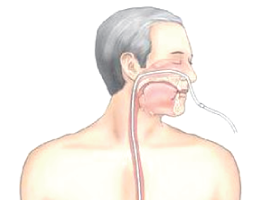

위루관, 비위관 삽입으로 입으로 식사를 못하는 경우

위루관, 비위관 삽입으로 입으로 식사를 못하는 경우